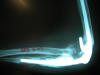

Fractura maleolo externo. Osteosíntesis.